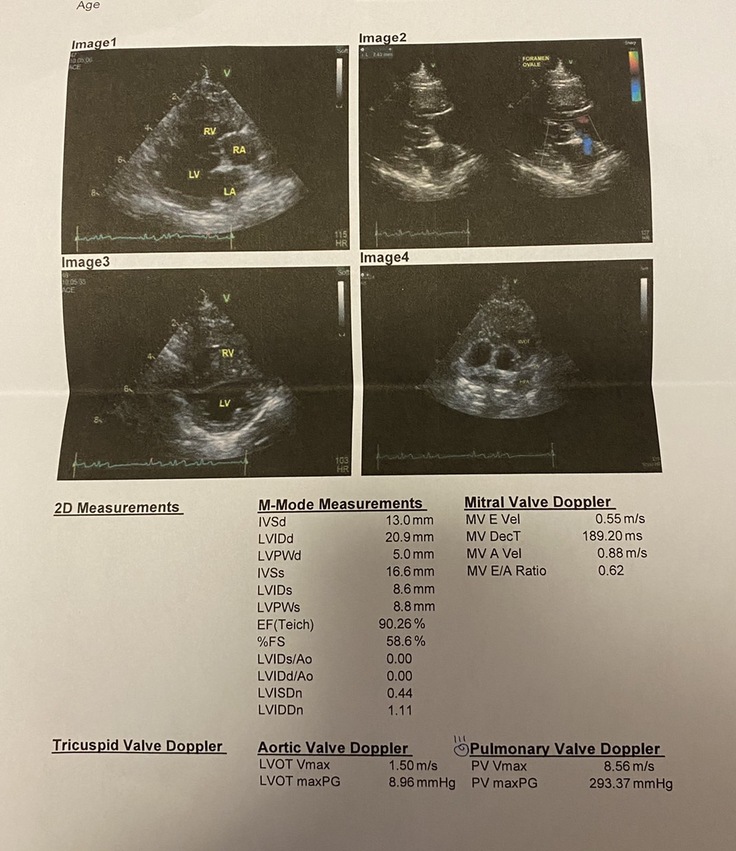

心臓の専門医にも『こんな数値は今までないくらい経験がないくらい重症度が高い。他の医師にも確認したがやはり見た事がない。』と言われてしまいました。

■肺動脈狭窄症とは?おもちはどんな状態?

二酸化炭素を多く含む全身を流れてきた血液は心臓の右心房➡右心室➡肺へと流れます。この右心室から肺へと血液を送る血管のことを肺動脈といいます。おもちはこの血管が細くなってしまっており、心臓から肺へ血液が流れにくいです。流れにくいところを右心室が頑張って肺へと血液を送り出そうとします。すると右心室が常に筋トレしている状態になります。その状態が続いてしまったので、おもちの右の心臓は筋肉ムキムキになってしまい、そのせいで右心室が狭くなってしまいました。(右心室肥大)

部屋が狭くなると、肺に送る血液が貯められません。ただでさえ細い道を通さなくてはいけないのに、血液を溜める所さえも小さくなってしまいました。

この状態が続くと心不全を起こし、呼吸が苦しくなったり、お腹に水が貯留してしまいます。

おもちは重度の狭窄病変があるため、失神を起こして突然倒れたり、呼吸が苦しくなります。

最終的にはうっ血性心不全(肺水腫や胸水、腹水貯留)を引き起こし呼吸困難に陥ります。

さらに、おもちは卵円孔開存があります。

心臓に穴が開いている状態です。

低酸素の状態が続いた為、多血症も併発しております。

■重症度

下記の表は重症度を表す表です。